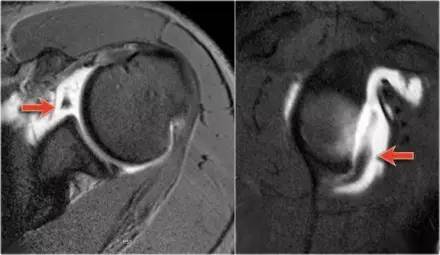

Bankart 损伤(来源:Radiology assistant)

Bankart 损伤的 MR 片 (来源:Radiology assistant)

骨性 Bankart 损伤的 MR(左)和 CT(右)(来源:ShoulderDoc)

骨性 Bankart 损伤的 MR(左)和关节镜图(右)(来源:ShoulderDoc)